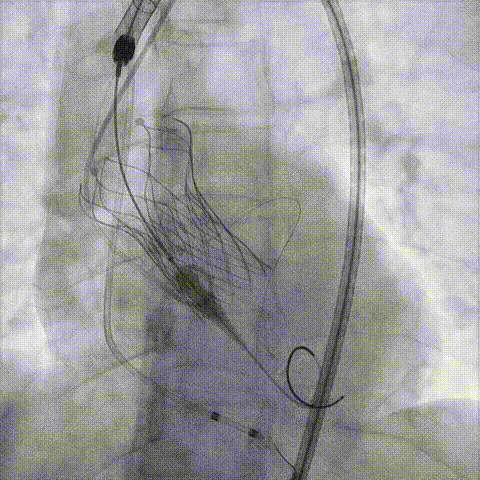

回收后调整深度,再次释放

评估左冠开口

左冠开口切线位造影

决定左冠烟囱支架保护冠脉

调整支架位置

释放冠脉支架

释放瓣膜

造影评估

支架内后扩张

冠脉造影

根部造影